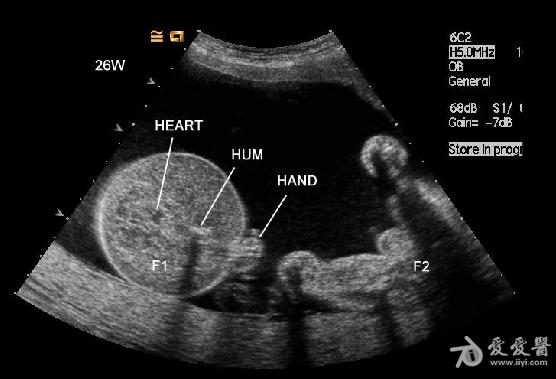

是双胎,其中畸形的那个明显没有上半身及头部,只有下半身和一点点短小的左上肢。

1、双胎中一胎形态、结构发育正常,另一胎出现严重畸形,以上部身体严重畸形为主,可有下部身体如双下肢等结构。

3、上部身体严重畸形,可表现为无头、无双上肢、胸腔发育极差。

无心畸胎序列征(acardiac twins sequence),也叫双胎反向动脉灌注序列征(twins reversed-artery perfusion sequence, TRAP);其特点是:双胎中一胎发育良好,而另一胎心脏不发育或发育不良,同时伴有其他多种严重畸形表现,并能作为受血儿通过异常的动脉-动脉吻合以接受发育良好的胎儿(泵血儿)的血供以继续生长。